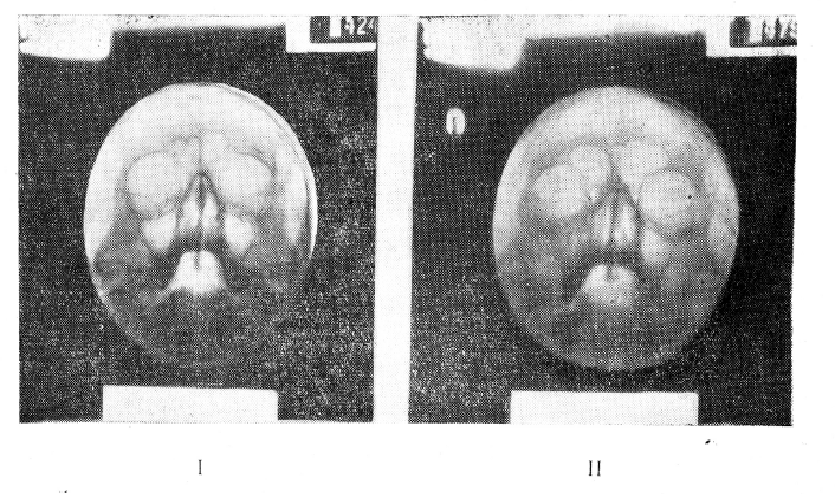

Из 76 больных с жидкостью в пазухах у 21 определялись горизонтальные уровни жидкости, у 14 — параболические границы, у 25 — сочетание жидкости и гиперплазии слизистой оболочки. Приводим несколько наших флюорографических наблюдений (рис. 1—I, II, III, IV).

Отображение патологических процессов в придаточных пазухах носа на флюорограммах имеет свои особенности. Так, пристеночные теневые наслоения в пазухах при острых катаральных и хронических гиперпластических процессах, а также полукруглые тени кист на флюорограммах представляются более интенсивными и подчеркнутыми, чем на рентгенограммах. В связи с исследованием больных в вертикальном положении, наличие жидкости в пазухах может давать на флюорограммах горизонтальные и параболические верхние контуры затенений. По той же причине кисты гайморовых полостей, уплощаясь, могут симулировать горизонтальные уровни жидкости, давая так называемый симптом уплощения кисты (А. И. Бухман). Однако при тщательном изучении флюорограмм в таких случаях удается заметить закругление «горизонтального уровня» книзу у наружной или медиальной стенок пазух. В сомнительных случаях правильно решить вопрос помогает рентгенография в горизонтальном положении больного. При этом киста приобретает обычные очертания с выпуклостью верхнего контура, а жидкость дает равномерное затенение пазухи.